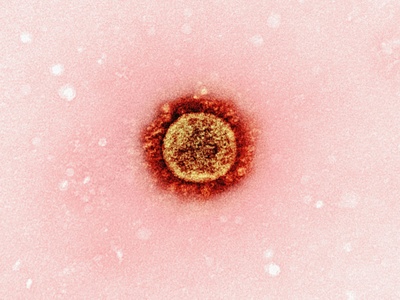

COVID-19

COVID-19 is caused by SARS-CoV-2, commonly producing fever, cough, fatigue and loss of smell; severe cases cause pneumonia and long-term symptoms. Global since 2019; spreads by respiratory routes. Vaccines and masks reduce risk; treatments and antivirals available for high-risk patients.